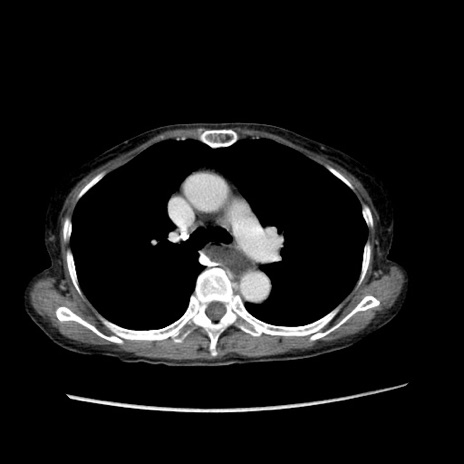

冠状断像

【症例】80歳代女性

【主訴】胸のつかえ感

【現病歴】約9時間前に食後から胸のつかえた感じあり、嘔吐あり、来院。

【既往歴】胃癌(全摘)、胆摘、虫垂炎

【身体所見】心窩部に圧痛あり、反跳痛なし。

【データ】WBC 5700、CRP 0.05